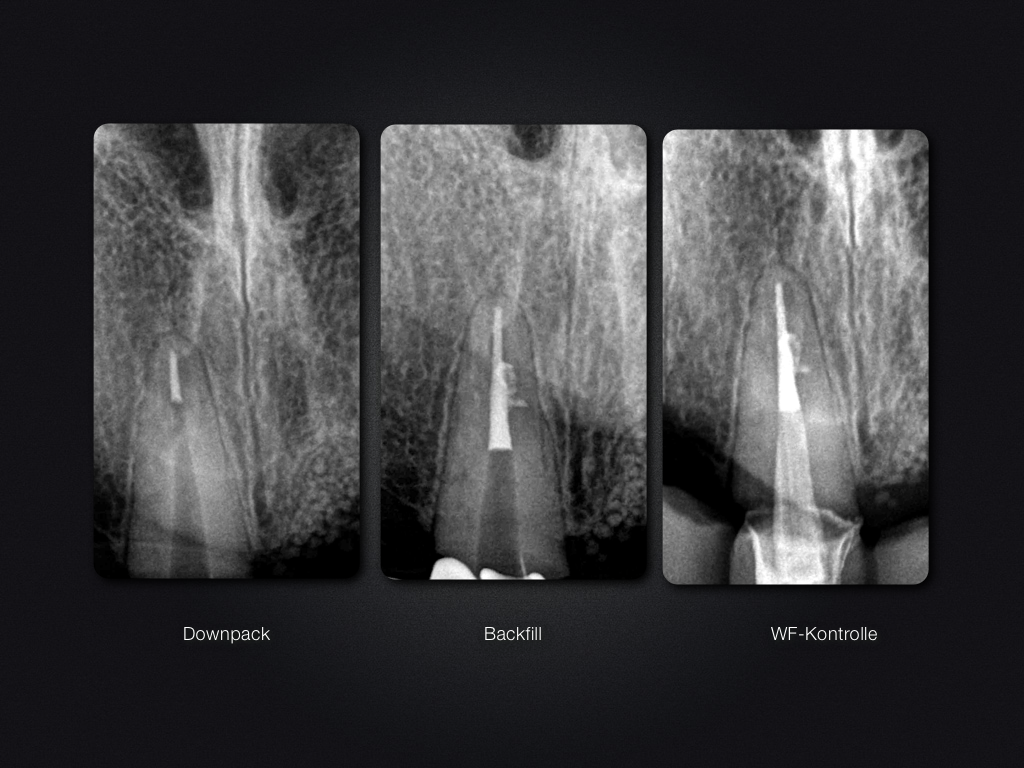

11D.005

Entwarnung